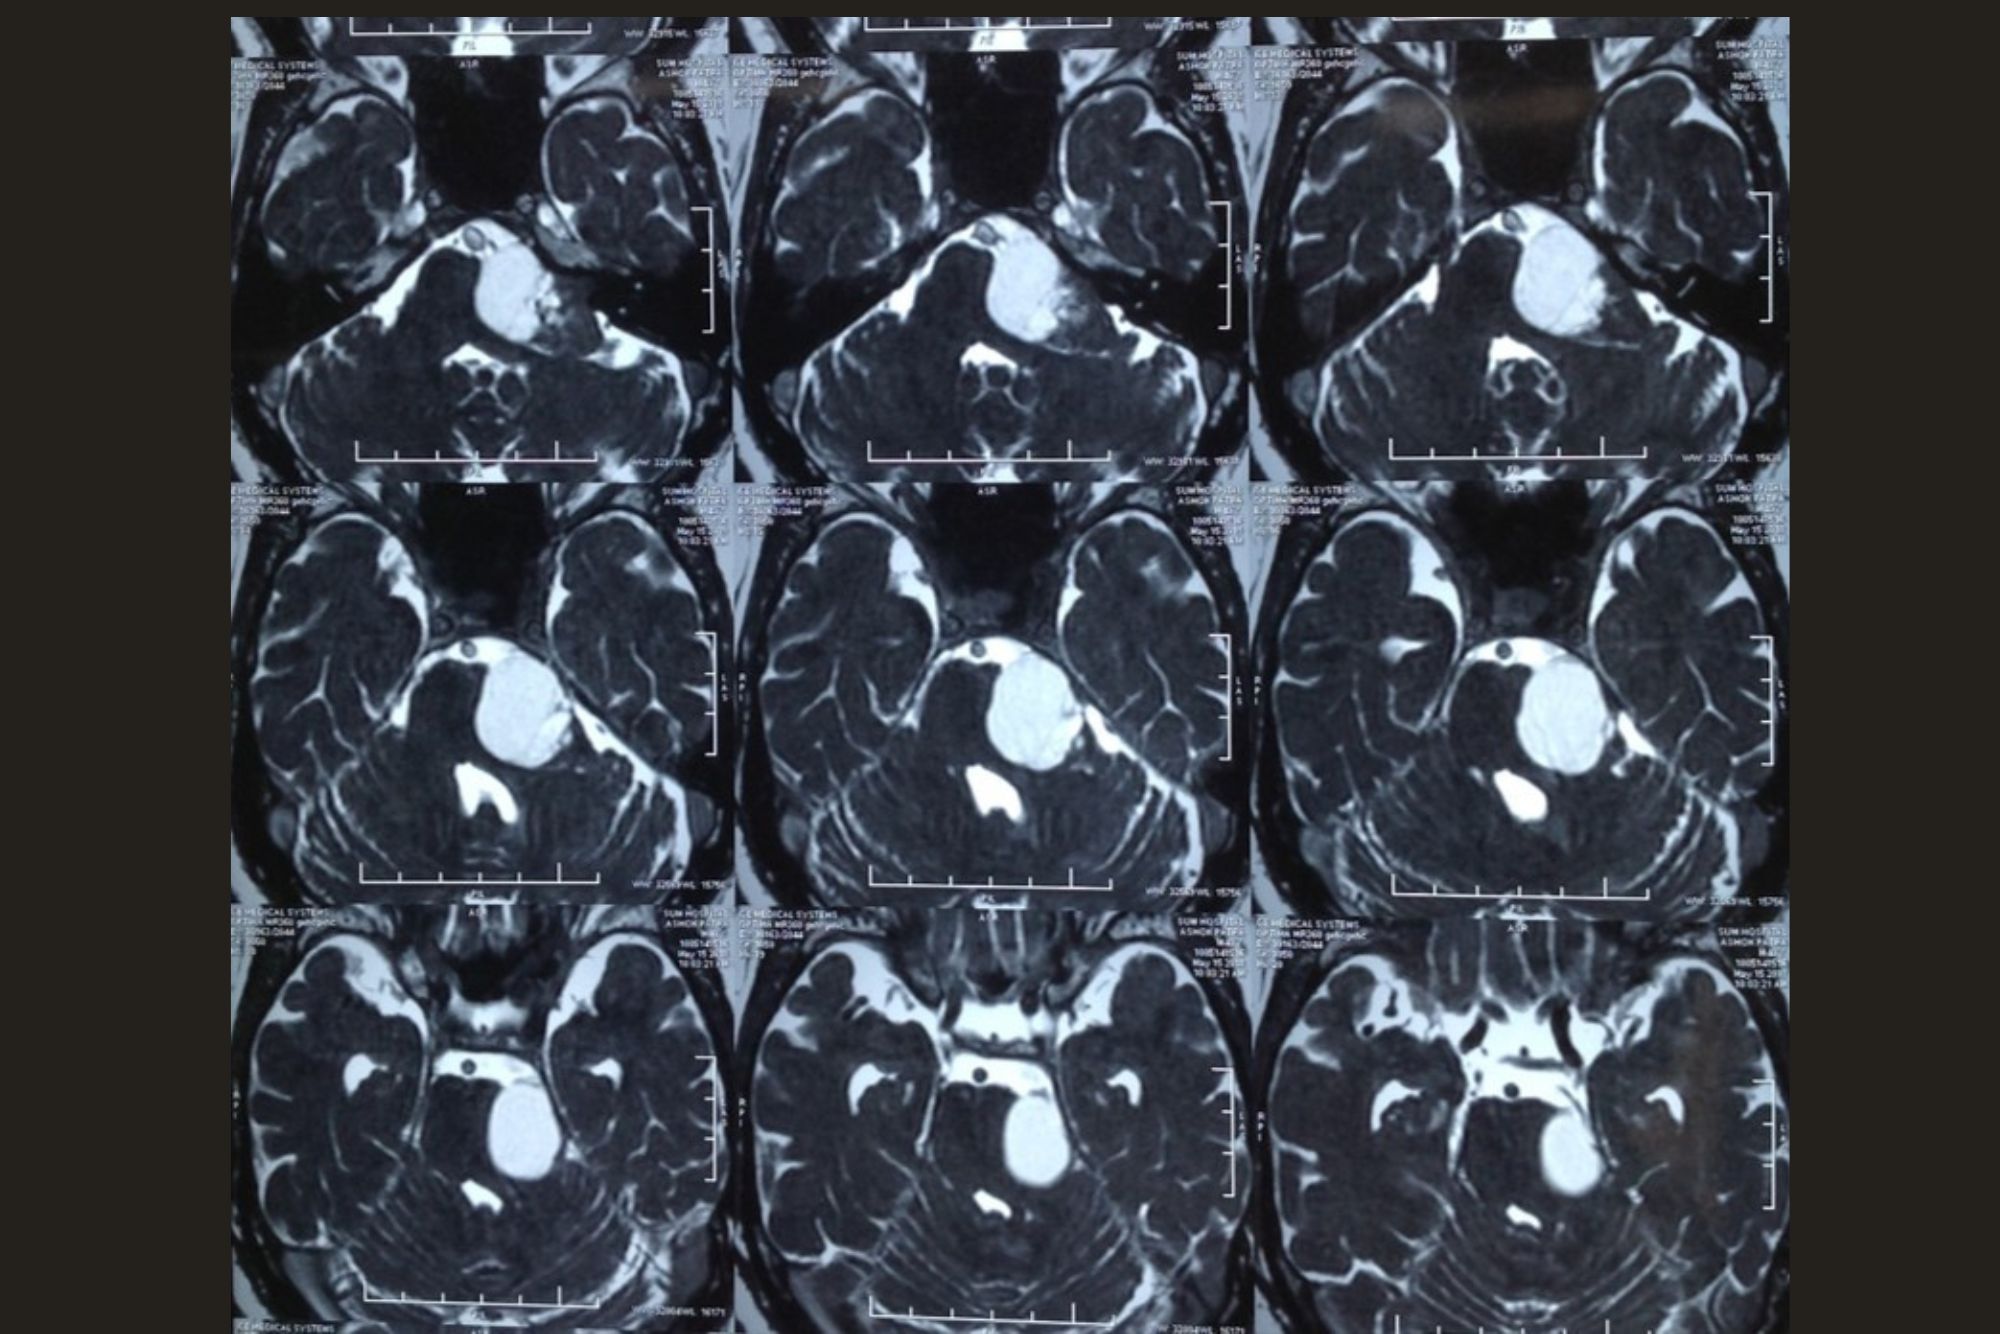

LEFT ACOUSTIC SCHWANNOMA

Preoperative MRI

4 MONTHS POST-OP